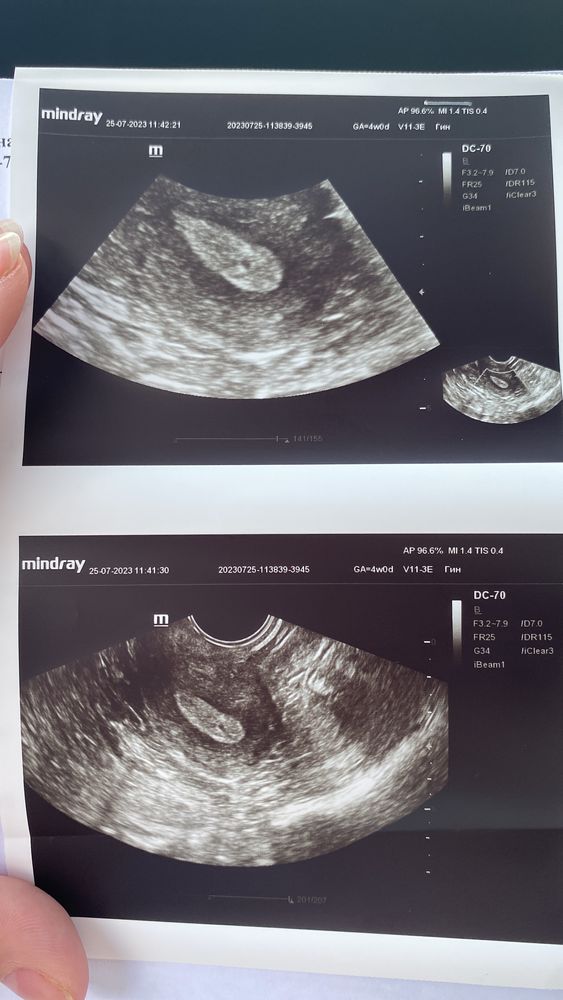

13 дпп 25.07 (вт) Хгч 420.1 t 37.5 По узи СВД 2.1

20 дпп 01.08 (вт) Беременность сохранить не удалось. 4 эмбр.недели СВД 6мм.